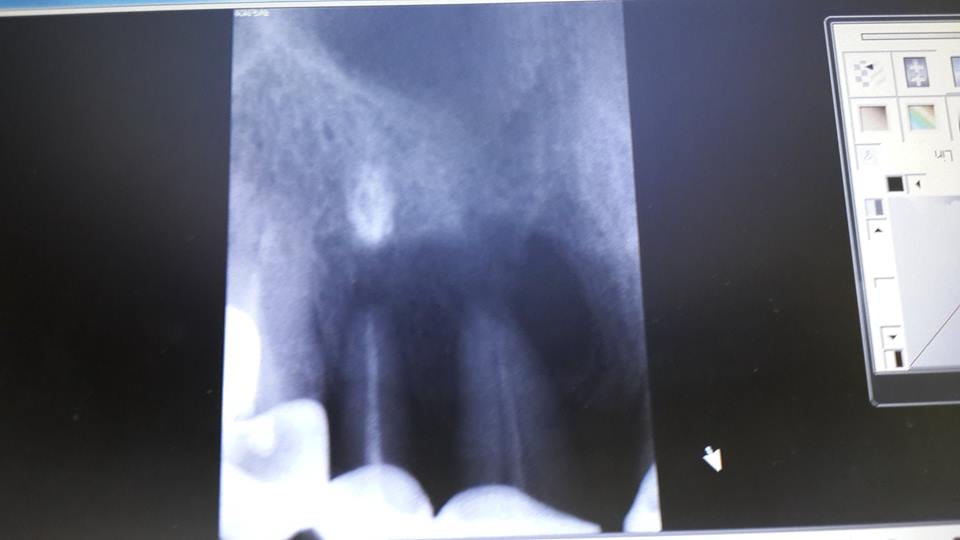

An example of complete rehabilitation of the oral cavity. Treatment included the removal of the old prosthesis, treatment of paradontitis, removal of a large cyst, implantation, clasp prosthesis.